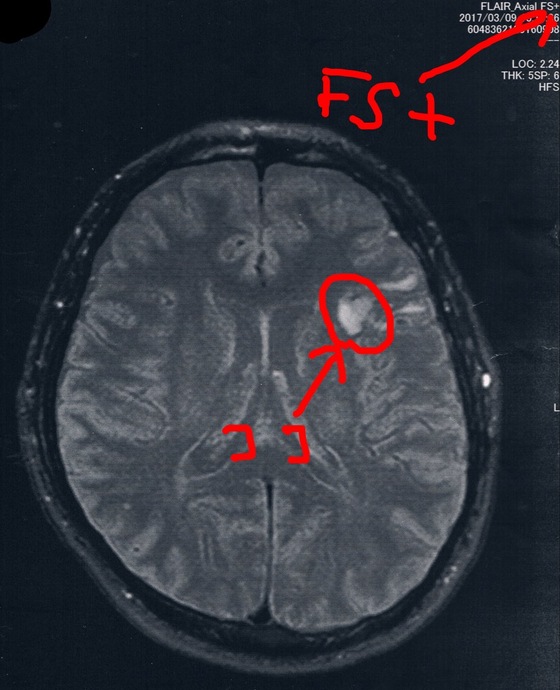

今回2017/3/9(手術後33か月)のMRI画像

前回と今回の画像で撮り方が違うらしくて白黒が違うのだけど、毎回おんなじMRI設備で同じ撮影方法で検査して欲しいなぁ。。。